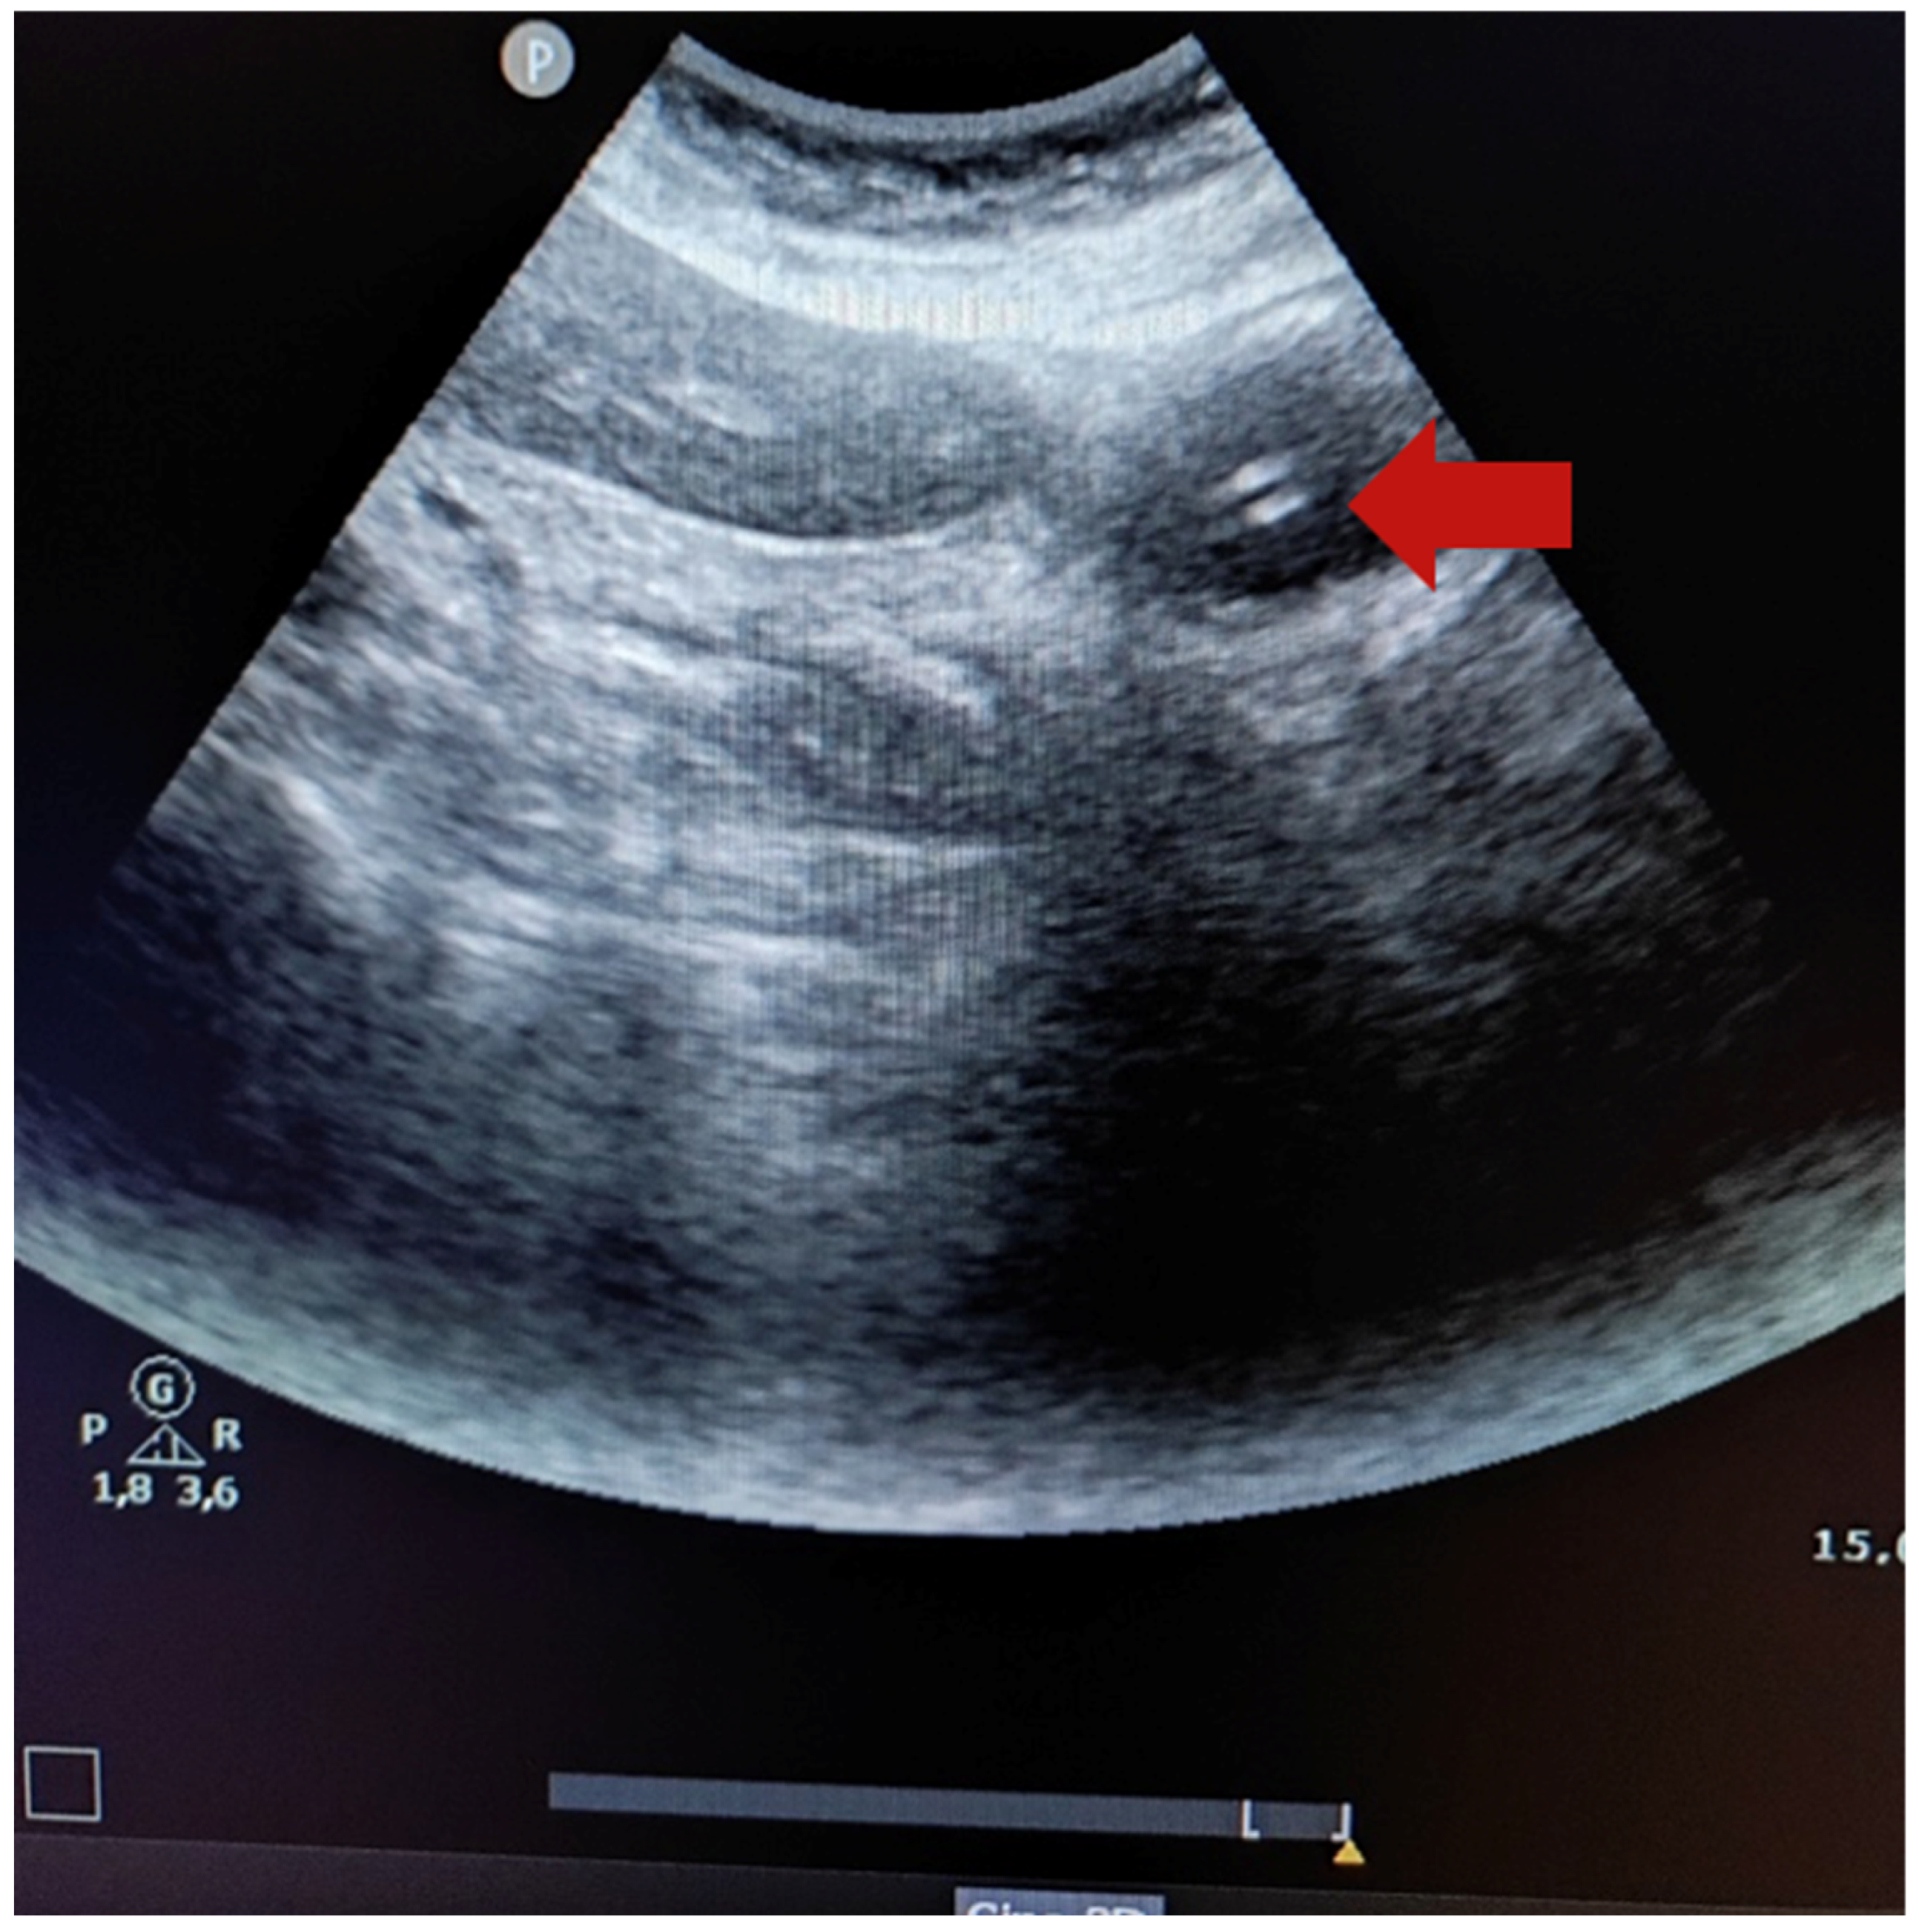

As for NGT indirect visualization through ultrasound, the intensive care nurse and physician reported that 7 NGTs (30.4%) were placed in the stomach, obtaining a sensitivity of 35.0% and specificity of 100%. However, through NGT indirect visualization using the “dynamic fogging” technique, the intensive care nurse verified that 17 NGTs (73.9%) were placed in the stomach, whereas the intensive care physician verified 18 NGTs (78.3%). Therefore, the sensitivity and specificity of the indirect visualization obtained by the intensive care nurse were 85.0% and 100%, respectively. These values were similar to values obtained by the intensive care physician (86.0% and 100% respectively) (Table 2). Figure 1 shows the ultrasound image of a 14-French gauge nasogastric tube placed in the stomach (the red arrow indicates two hyperechogenic parallel lines).

Figure 1. Ultrasound image of a 14-French gauge nasogastric tube placed in the stomach (the red arrow indicates two hyperechogenic parallel lines).